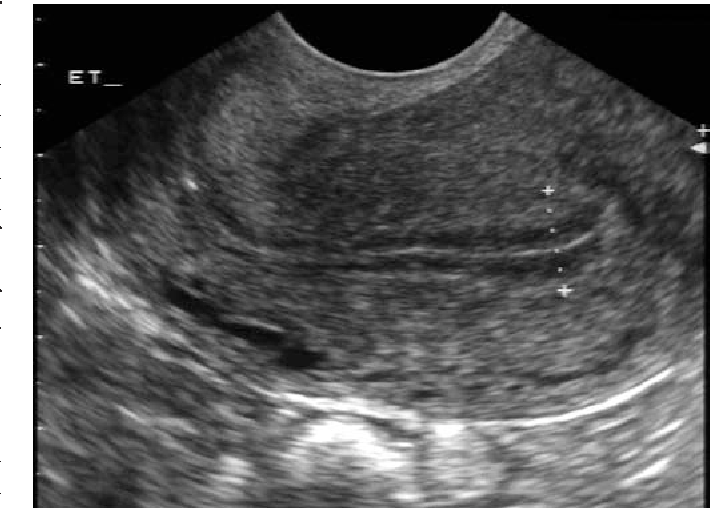

етрия на узи

Утолщения эндометрия на узи 113 фотографий